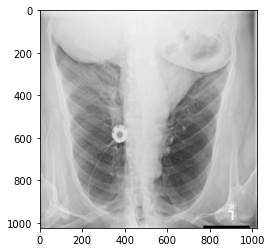

Filename.........: ../dicom/train_images/1.2.276.0.7230010.3.1.4.8323329.300.1517875162.258081.dcm

Storage type.....: 1.2.840.10008.5.1.4.1.1.7

Patient name.....: 88c14312-3265-4a3f-b7bb-41818107d607,

Patient ID.......: 88c14312-3265-4a3f-b7bb-41818107d607

Patient Age......: 58

Patient Sex......: F

Modality.........: CR

Body Part........: CHEST

View Position....: AP

Image size.......: 1024 x 1024, 154050 bytes

Pixel spacing....: [0.139, 0.139]